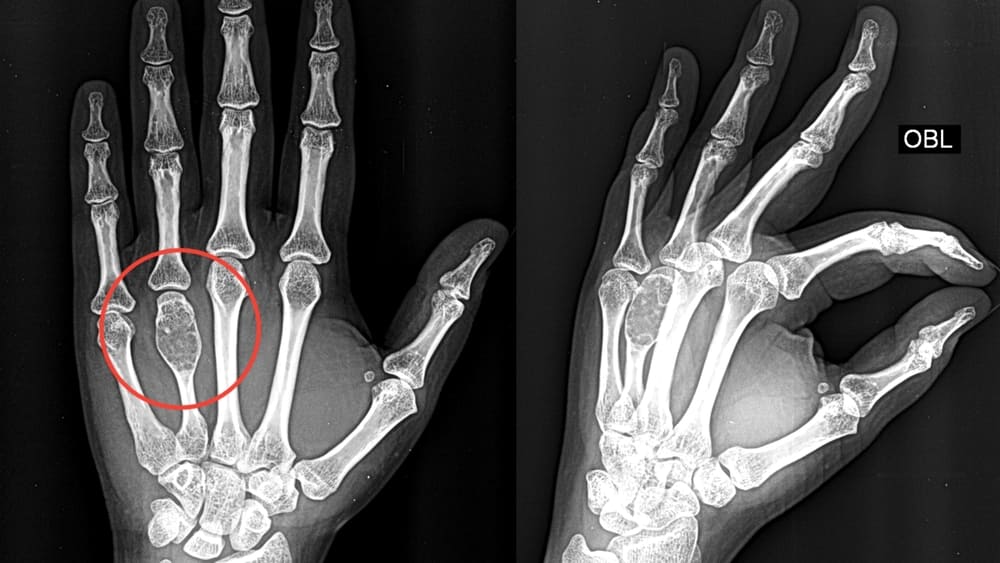

Особняком стоят костные опухоли. Часто встречаются остеомы, доброкачественные костные опухоли. Чаще всего они медленно растут и обычно не вызывают симптомов. Остеомы могут быть обнаружены случайно при рентгенологическом исследовании. Другой вариант — остеоид-остеомы: небольшие доброкачественные опухоли кости, часто характеризуется ночными болями, которые эффективно снимаются нестероидными противовоспалительными препаратами. Наконец, встречаются остеобластомы, доброкачественные опухоли, похожие на остеоид-остеомы, но значительно большего размера. Они вызывают боли и иногда приводят к патологическим переломам. Остеобластомы встречаются реже и ведут себя агрессивнее. Все новообразования так или иначе требуют лечения.

- рентгенография;

- Очкуренко А.А., Молов Х.Х. Локализация доброкачественных опухолей, опухолеподобных и воспалительных заболеваний в костях кисти. Медицина Кыргызстана. №3. 2012 г. 182-183 с.

- Котельников Г.П., Колсанов А.В., Николаенко А.Н., Попов Н.В., Щербовских А.Е., Иванов В.В., Приходько С.А., Платонов П.В. Хирургическое лечение доброкачественных опухолей и опухолеподобных заболеваний костей кисти. Хирургия. Журнал им. Н.И. Пирогова. 2018;(1):86‑89.